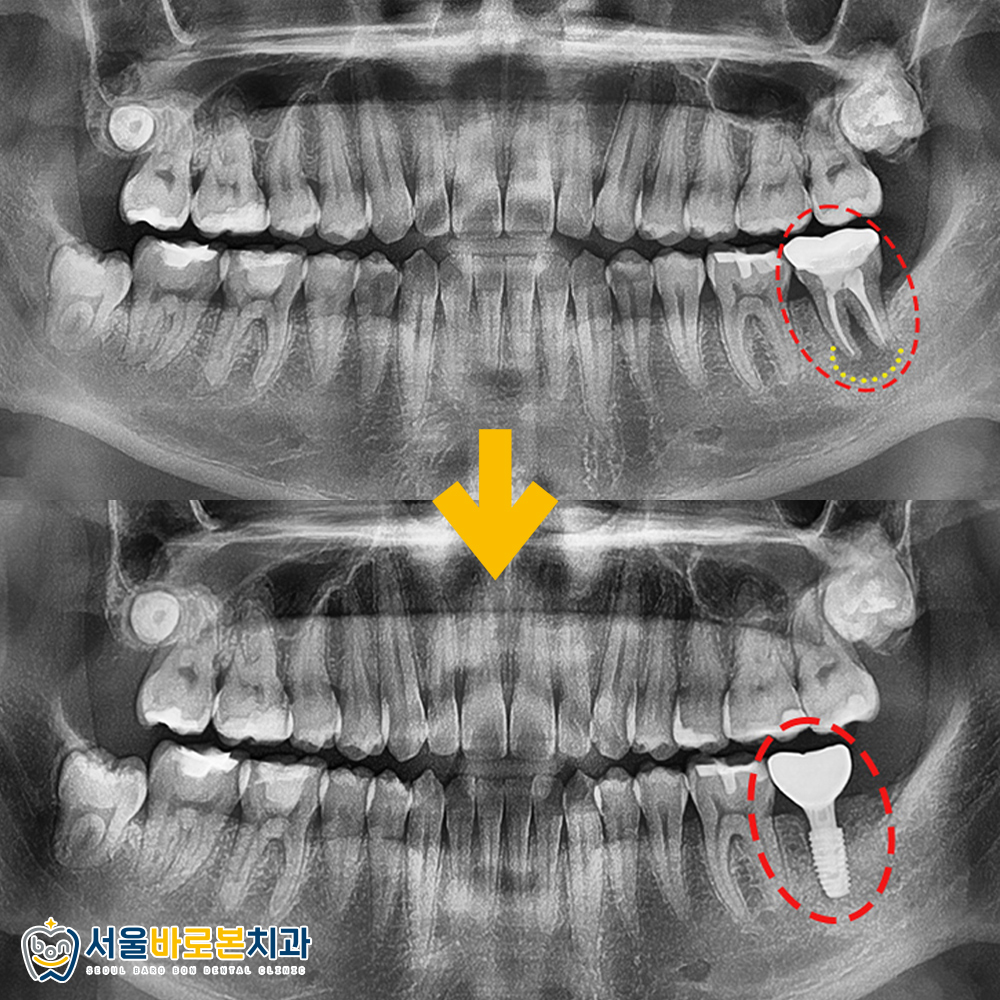

정밀한 체크를 위해

파노라마 사진을 촬영해 보았더니

불편감을 느끼고 있던 치아는

과거 신경치료 및

크라운 수복을 한 치아로

치아 뿌리 주변으로

심한 염증을 관찰할 수 있었는데요.

잇몸뼈가 녹아 뿌리 끝 주변으로

까맣게 비춰보이는 부분을 확인할 수 있으며,

잇몸뼈가 치아의 뿌리 부분만 잡고 있어

동요도까지 보이는 상황이었습니다.

심한 염증으로 인해 신경 가까이까지

치조골이 흡수된 위험한 상황이었답니다!

발치와 보존술로

뼈가 잘 회복된 것을 확인한 후

임플란트 수술을 도와드렸습니다.

현재는 치아 뿌리 역할을 하는

인공치근인 픽스처만 식립되어 있는 상태이고,

픽스처가 잇몸뼈에 잘 유착된 것을 확인한 후

치아 머리 역할을 하는 크라운(보철물)을 올려

치료를 마무리 하게 됩니다.